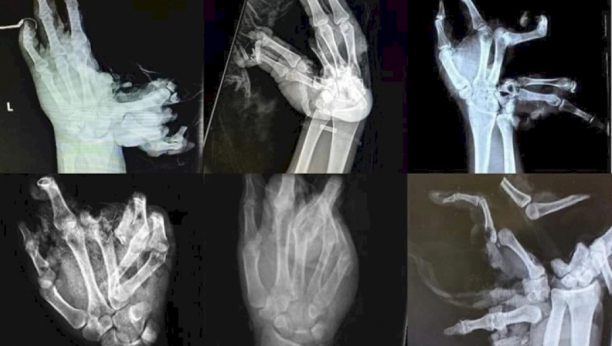

OVAKO IZGLEDA KADA VAM PUKNE PETARDA U RUCI "Šaka je obično u najlonu, iz nje curi krv, padaju komadi koste i kože!

- „10 godina smo suprug i ja radili u Hitnoj pomoći. Sa nelagodom iščekujemo raspored dežurstava jer se ni jedan zdravstveni radnik ne raduje tom dežurstvu... A onda dođe 31. decembar. pesnica je u najlonu i peškiru, iz kojeg curi krv i padaju komadi kosti i kože u čekaonici zbog neveštog držanja uplakanih roditelja ili prijatelja koji su u strašnom šoku da je u stvarnosti 1000 puta strašnije + bolovi će biti brzi, ako i jedan prst može da se sačuva za sekundu euforije, ceo život će platiti invalidninom, zbogom društvo, zbogom , zbogom posla, najčešće je otac bio odgovoran za petardu u ruci deteta. Zato ako voliš sebe i druge, imaš divne planove, i srećan i bezbrižan život, onda ostavi petardu. onima koji su odlučili da budu nepovratno nesrećni“